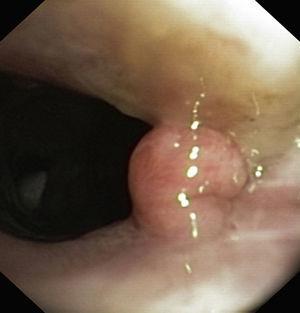

Figures 3 and 4. This broad based tracheal papilloma was debulked with an electrocautery snare and extended with cryo-coagulation of the base.

| Significant obstruction of the trachea (>80%) | Exophytic mass obstructing 80% of the tracheal lumen ( Fig. 3 ) | |||

| 1° line endoscopic treatment | Removal of the tracheal mass by an electrocoagulation snare | Removal of the tracheal mass by an electrocoagulation snare ( Fig. 4 ) | Intralesional administration of cidofovir at the left vocal cord ( Fig. 5 ) | Nd:YAG laser vaporization in the larynx and tracheal lesions (Fig. 8) |

| Coagulation of the tracheal tumor base with Nd:YAG laser ( Fig. 2 ) | Photocoagulation of the tracheal lesions with Nd:YAG laser ( Fig. 4 ) | No complications | Local administration of cidofovir at the base of the tracheal papillomas | |